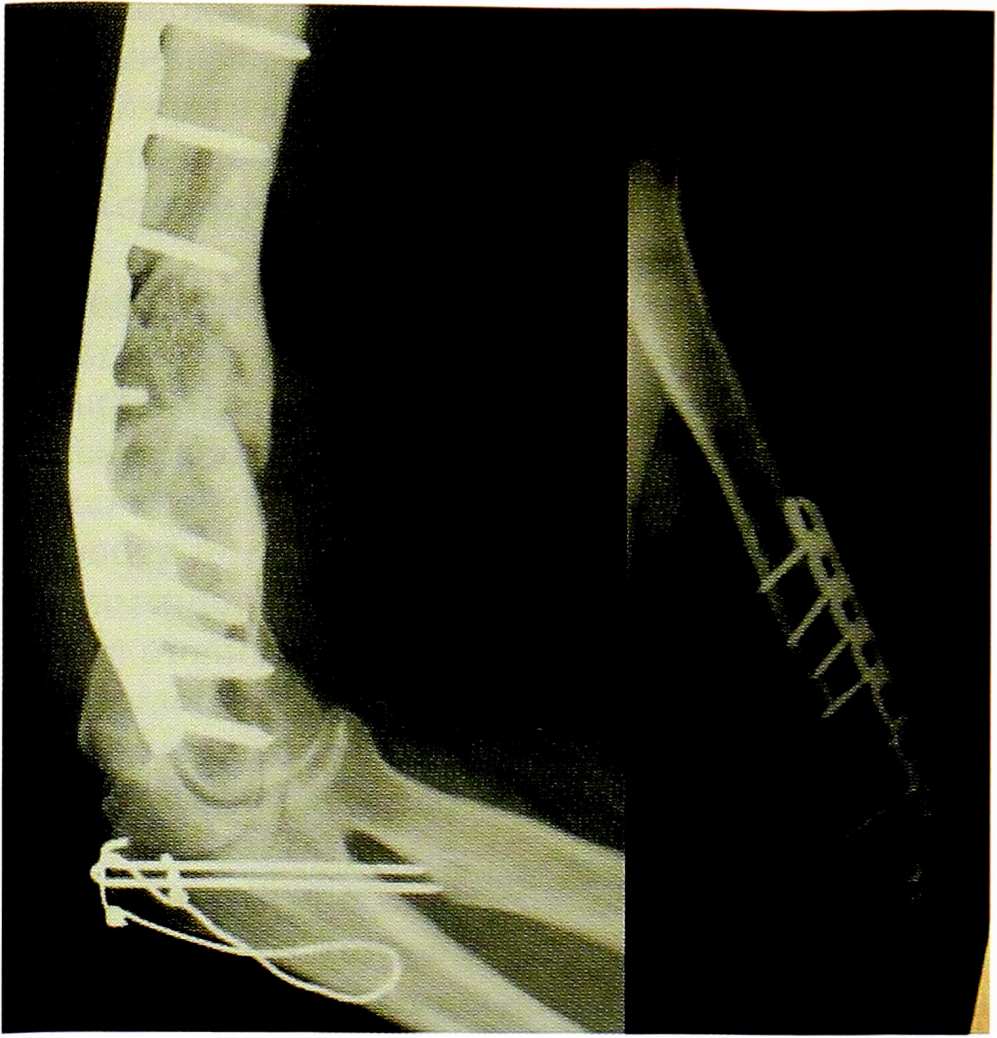

Рис. 11. Пациентка H. Оперативное лечение: резекция зоны ложного сустава левой плечевой кости, остеосинтез пластиной и винтами. Пластика свободным кровоснабжаемым трансплантатом из внутреннего мыщелка бедренной кости.

Fig. 11. Patient N. Surgical treatment: resection of the zone of the false joint of the left humerus, osteosynthesis of the plasty and screws. Plastic free perfused TRANSplantation from the internal condyle of the femur.

Рис. 12. Рентгенограммы пациентки H. после операции.

Fig. 12. Radiographs of patient N. after surgery.

Рис. 13. Рентгенограммы пациентки H. через 8 мес после операции.

Fig. 13. Radiographs of patient N. 8 months after surgery.